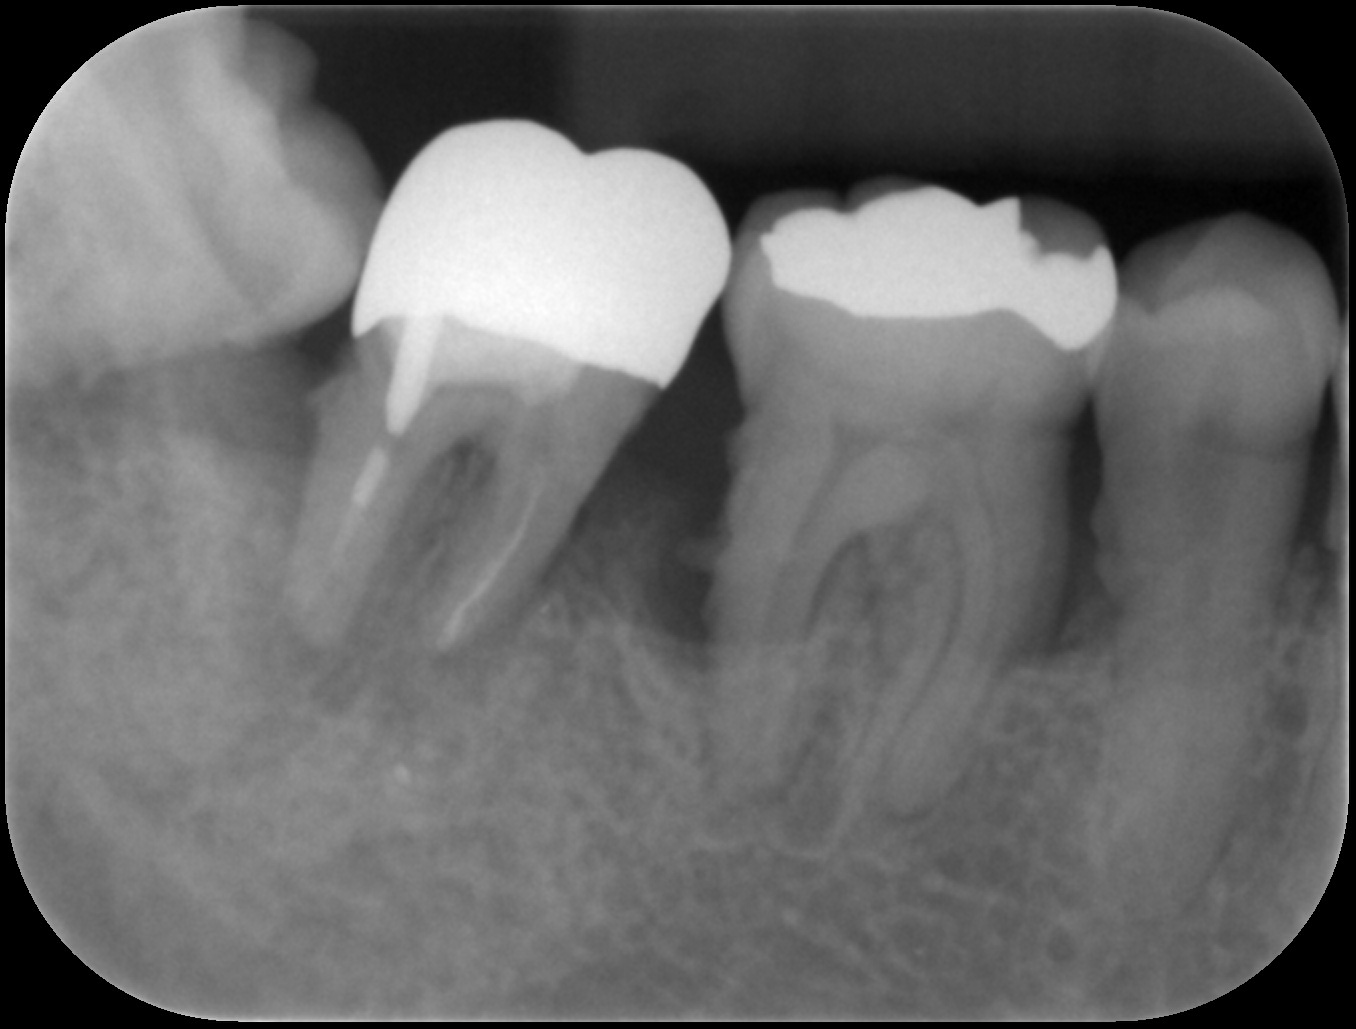

初診時

歯周基本治療後

歯周組織再生療法後6ヶ月

| 主訴 | 他院にて歯周病と診断され、抜歯するしかないと言われたが年齢的(初診時30代)に抜歯はしたくない。 歯周病の専門医に相談した方がいいと言われ当院を受診。 |

| 治療内容 | 精密検査の結果、歯周ポケット(歯と歯茎の間の溝)4mm以上の部位が全体の67%、最大11mmの歯周ポケットを認めた。*歯周ポケットの正常値は3mm以下。 またエックス線画像からは奥歯を中心に歯槽骨(歯を支える骨)の著しい吸収を認めた。 ブラッシング指導、歯肉縁上歯石の除去、歯肉縁下歯石の除去、根管治療を行った後、再評価検査を行った結果、全顎的に歯周外科治療が必要であったため歯周組織再生療法を行った。 |

| 治療期間 | 9ヶ月 歯周基本治療(2ヶ月) 歯周外科治療、歯周組織再生療法(2ヶ月) 歯周組織再生療法後は6ヶ月経過を確認しメインテナンスへ |

| 費用 | 歯周組織再生療法(サイトカイン+骨補填剤の併用療法) 165,000(1部位につき) |

| リスク・副作用 | サイトカインと骨補填剤を併用した歯周組織再生療法では術後の腫れや痛みを生じる場合があります。 歯周組織(特に歯槽骨)の再生が認められた後も定期的なメインテナンスやご自身でもブラッシングが大切です。それを怠ると再発や悪化につながりますのでご注意ください。 *当院ではブラッシング指導を徹底し、ご自身できちんと口腔内環境を管理できるようご協力いただいております。ブラッシング状況が改善されない場合は歯周外科治療へ進まないこともありますのでご理解ください。 |